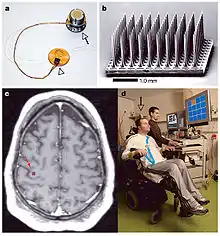

History of electrodes in the brain: In 1878 Richard Caton discovered that electrical signals transmitted through an animal's brain. In 1950 Dr. Jose Delgado invented the first electrode that was implanted in an animal's brain, using it to make it run and change direction. In 1972 the cochlear implant, a neurological prosthetic that allowed deaf people to hear was marketed for commercial use. In 1998 researcher Philip Kennedy implanted the first brain–computer interface (BCI) into a human subject.[17]